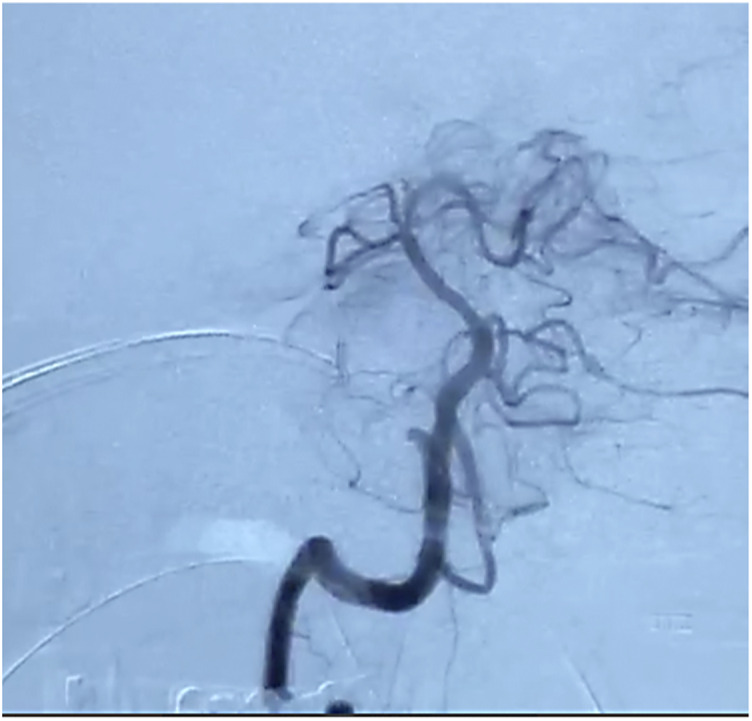

Case presentation: We present the case of a 64-year-old male diagnosed with basilar artery occlusion who underwent a successful mechanical thrombectomy 11 days after symptom onset. Despite complications such as hemorrhagic transformation and herniation, the patient was stabilized and showed functional improvement 3 months post-stroke.